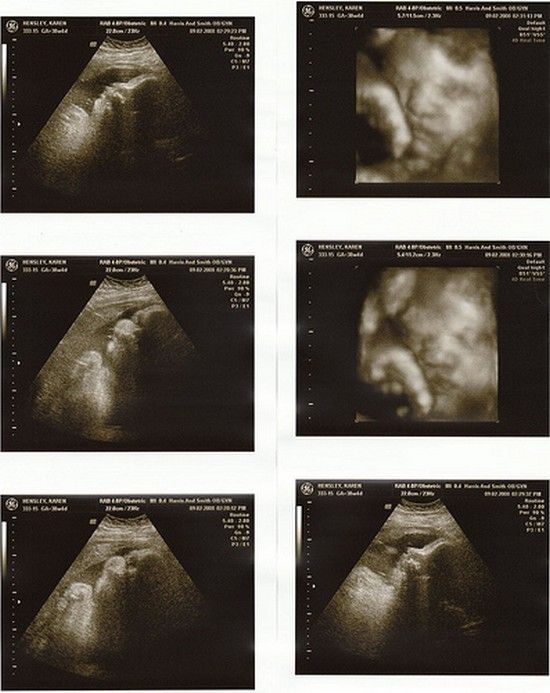

Плод 39 Недель Фото

Плод 39 Недель Фото 100 фото